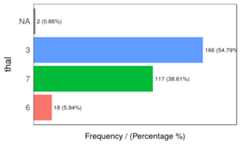

freq(data=heart_disease,input =c('thal','chest_pain'))

Figure 1.2: Frequency analysis 1

## thal frequency percentage cumulative_perc## 1 3 166 54.79 54.79## 2 7 117 38.61 93.40## 3 6 18 5.94 99.34## 4 <NA> 2 0.66 100.00

Figure 1.2: Frequency analysis 2

## chest_pain frequency percentage cumulative_perc## 1 4 144 47.52 47.52## 2 3 86 28.38 75.90## 3 2 50 16.50 92.40## 4 1 23 7.59 100.00## [1] "Variables processed: thal, chest_pain"As well as in the remainingfunModeling functions, ifinput is missing, then it will run for all factor or character variables present in a given data frame: